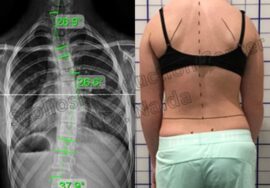

ما هي زاوية كوب؟

زاوية كوب هي الأداة الطبية الأكثر اعتمادًا لقياس شدة انحناء العمود الفقري. ابتكرها الجرّاح الأمريكي جون كوب، وتُستخدم لتحديد:

كيف يتم قياس زاوية كوب؟

تصوير الأشعة: يُجرى للمريض وهو واقف أو مستلقٍ.

تحديد الفقرات النهائية: اختيار الفقرة الأكثر ميلًا في أعلى وأسفل الانحناء.

رسم الخطوط: رسم خطين على الفقرات المائلة ثم قياس الزاوية الناتجة.

يتميز هذا القياس بالدقة، لكنه قد يتأثر ببعض العوامل مثل: وضعية المريض، اختلاف تقييم الأطباء، ودوران الفقرات.